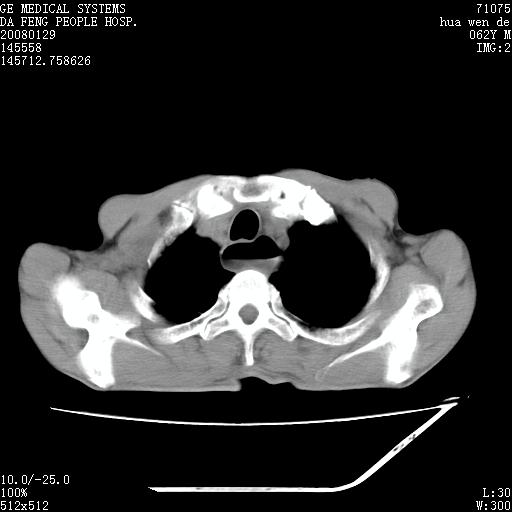

男性,67岁。作肺部检查时发现

考虑:胸腔胃并支气管瘘(并发肺炎,肺脓肿形成)。

理由:1、右上肺内病灶,空洞形成,有液平。

2、肺内多处炎症。

1.整个食管扩张,未见明显占位性病变,贲门区亦未见明显占位病变,考虑:贲门失驰缓症;

食管全程扩张,壁均匀不厚,喷门失弛缓症

右上肺空洞可见液平,临近肺野磨玻璃密度,考虑1.结核2.脓肿

贲门失驰缓症.肺部感染伴脓肿形成。支持!是否吸入性要结合临床诊断,我们影像是看不出来的。但胸腔胃能排除(1.没有手术史支持,2.双侧胸廓对称,胸壁、肋骨及胸膜规整,3,食管壁明显扩张内壁光滑,胸腔胃黏膜皱襞多较厚)。